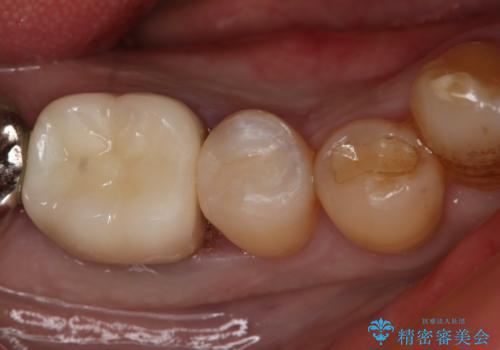

下の奥歯の銀歯を白くしたい

- 左下奥歯のメタルインレーを白くしたいと希望された患者様です。

形態、切削量などを考慮し、セラミックインレーにて治療を行いました。

メタルインレー、う蝕除去後にCRにて裏層した上で、形成・印象を行いました。